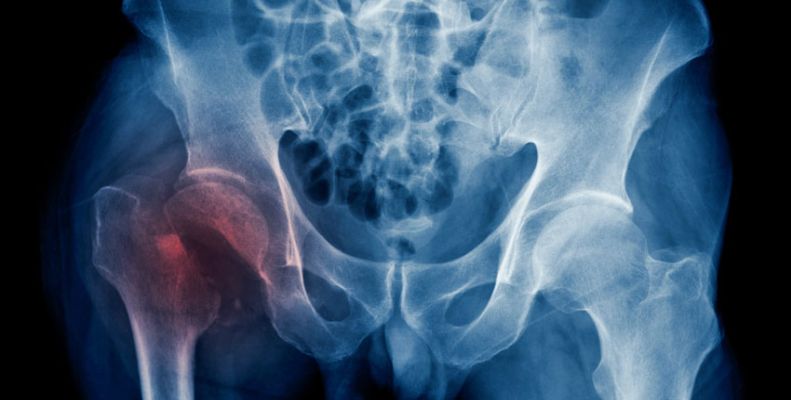

Σημαντική αύξηση των καταγμάτων ισχίου έως το 2050

Διεθνής μελέτη που περιελάμβανε ερευνητές από την Ιατρική Σχολή του Χάρβαρντ δείχνει ότι ενώ τα ποσοστά εμφάνισης καταγμάτων ισχίου σύμφωνα με την ηλικία και το φύλο έχουν μειωθεί στις περισσότερες χώρες του κόσμου, ο αριθμός των καταγμάτων ισχίου παγκοσμίως προβλέπεται συγκριτικά με το 2018, να διπλασιαστεί μέχρι το 2050 πλήττοτντας κυρίως τους άνδρες.

Η μελέτη, που δημοσιεύθηκε πρόσφατα στο Journal of Bone and Mineral Research, εξέτασε περισσότερες από 4 εκατομμύρια περιπτώσεις και υπογραμμίζει την επείγουσα ανάγκη για καλύτερες στρατηγικές για την πρόληψη και τη φροντίδα των καταγμάτων ισχίου.

Η μείωση των καταγμάτων ισχίου σε πολλές χώρες τα τελευταία χρόνια δεν είναι αρκετή για να αντισταθμίσει τον αντίκτυπο της γήρανσης του πληθυσμού.

Δεδομένου ότι το κάταγμα ισχίου δεν είναι μόνο ιατρικό ζήτημα, αλλά και κοινωνικό ζήτημα που συχνά απαιτεί ιδρυματοποίηση, η μελέτη έδειξε ότι η κυβερνητική πολιτική και η διεπιστημονική παρέμβαση θα πρέπει να ληφθούν υπόψη για τη μείωση των επιπτώσεων του κατάγματος ισχίου τα επόμενα 30 χρόνια.

Οι ερευνητές αξιολόγησαν τις παγκόσμιες τάσεις στη συχνότητα καταγμάτων ισχίου, τα πρότυπα θεραπείας μετά από κάταγμα ισχίου και τη θνησιμότητα από κάθε αιτία από το 2005 έως 2018.

Στη μελέτη, οι ερευνητές είχαν άμεση πρόσβαση στα δεδομένα από μια μεγάλη αντιπροσωπευτική μελέτη κοόρτης που περιελάμβανε 19 χώρες και περιοχές για να εξετάσουν τη συχνότητα εμφάνισης καταγμάτων ισχίου, τη θεραπεία μετά από κάταγμα ισχίου και τη θνησιμότητα από κάθε αιτία μετά από κατάγματα ισχίου σε ασθενείς ηλικίας 50 ετών και άνω.

Συνολικά 4.115.046 περιπτώσεις κατάγματος ισχίου εντοπίστηκαν στη μελέτη κοόρτης. Τα αναφερθέντα τυποποιημένα ποσοστά επίπτωσης κατά την ηλικία και το φύλο των καταγμάτων ισχίου κυμαίνονταν από 95,1 (Βραζιλία) έως 315,9 (Δανία) ανά 100.000 πληθυσμού.

Οι περισσότερες χώρες και περιοχές εμφάνισαν πτωτική τάση στη συχνότητα εμφάνισης καταγμάτων ισχίου, με τις πιο έντονες μειώσεις στη Δανία, -2,8 τοις εκατό ετησίως, στη Σιγκαπούρη, -2,8 τοις εκατό και στο Χονγκ Κονγκ, -2,4 τοις εκατό.

Οι μεγαλύτερες αυξήσεις σημειώθηκαν στην Ολλανδία, +2,1 τοις εκατό και στη Νότια Κορέα, +1,2 τοις εκατό.

Παρά τη συνολική μείωση της συχνότητας καταγμάτων ισχίου, ο συνολικός αριθμός καταγμάτων ισχίου εκτιμάται ότι θα διπλασιαστεί συγκριτικά με το 2018 έως το 2050.

Μέσα σε ένα χρόνο μετά από ένα κάταγμα ισχίου, η θεραπεία μετά το κάταγμα παρέμεινε χαμηλή όλα αυτά τα χρόνια, κυμαινόμενη από 11,5 τοις εκατό στη Γερμανία έως 50,3 τοις εκατό στο Ηνωμένο Βασίλειο.

Τα ποσοστά θνησιμότητας από κάθε αιτία εντός  ενός έτους κυμαίνονταν από 14,4 (Σιγκαπούρη) έως 28,3 τοις εκατό (Ηνωμένο Βασίλειο), ενώ οι τάσεις θνησιμότητας κυμαίνονταν από -5,3 έως +18,4 τοις εκατό ετησίως.

Οι άνδρες είχαν χαμηλότερη χρήση φαρμάκων κατά της οστεοπόρωσης από τις γυναίκες, υψηλότερα ποσοστά θνησιμότητας από κάθε αιτία και μεγαλύτερη αύξηση στον προβλεπόμενο αριθμό καταγμάτων ισχίου μέχρι το 2050.